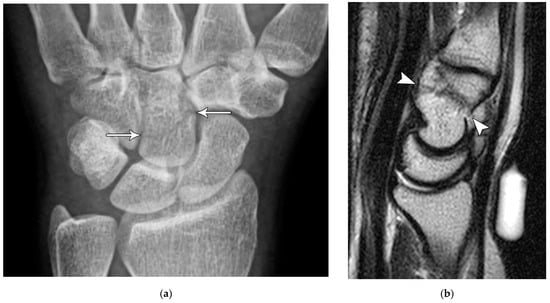

Figure 4. (a) Lateral radiograph of the wrist showing Humpback deformity (arrow) after a scaphoid fracture. (b) Sagittal CT reformation of the wrist showing the full extent of a humpback deformity with dorsal prominence at the site of the scaphoid fracture (arrowheads); image courtesy of Frank Gaillard, Radiopaedia.org, rID: 18269.

The majority of scaphoid fractures (70%) occur through the waist of the scaphoid, with 10% of scaphoid fractures involving the distal third, and 20% involving the proximal third (Figure 2 and Figure 3) [2,14]. With a scaphoid waist fracture, dorsal prominence at the fracture site due to dorsal angulation is known as humpback deformity (Figure 4). This deformity is important to recognize, as it needs to be more aggressively managed due to high risk of nonunion [15]. Additionally, if the two fragments unite with a humpback deformity, it may further destabilize the wrist. This humpback deformity may also be associated with dorsal intercalated segment instability (DISI), which will be covered in more detail later.